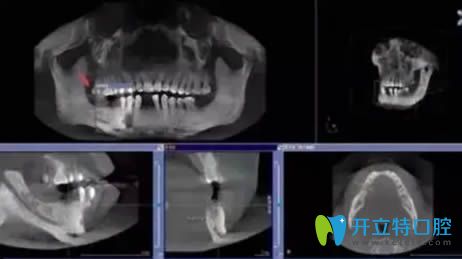

廣州瑞泰口腔在醫(yī)療設(shè)備和醫(yī)生團(tuán)隊(duì)的配備上都達(dá)到了高、精、尖的水準(zhǔn),采用全套化的進(jìn)口醫(yī)療影像設(shè)備,嚴(yán)格遵循美國齒科協(xié)會(huì)的(ADA)標(biāo)準(zhǔn)進(jìn)行消毒,杜絕交叉感染。院內(nèi)設(shè)有25張牙椅,開設(shè)有口腔正畸、牙齒種植、兒童齒科、牙周病、美學(xué)修復(fù)項(xiàng)目。

郭航院長——微創(chuàng)種植、上頜竇提升術(shù)、復(fù)雜種植修復(fù)、無牙頜All-on-4種植、多牙缺失種植及數(shù)字化CAD/CAM牙齒美容修復(fù)。